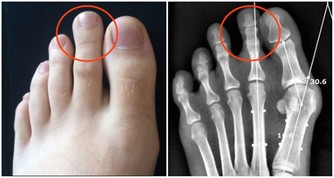

***1、指甲易斷***

中醫認為,指甲質地堅硬,是肝血充足的體現。如果指甲開始變脆,容易劈裂,則表明肝血不足、筋失所養。

***2、指甲豎線***

正常人的指甲,是表面光滑,無痕蹟的。如果指甲開始變得粗糙,並且豎線增多,則表明肝陰、肝血不足,也可能是肝功出現了異常。如果是熬夜,或是勞累導致指甲豎線增多,往往是與肝臟過度消耗有關。

***3、指甲發黃***

如果肝經內有濕熱,身體某部位就會發黃,比如指甲發黃。另外,肝臟不好的人,舌苔和眼睛也會發黃,嚴重者臉部肌膚也會發黃。

***4、凹凸不平***

如果指甲並不光滑,而是有一條一條的橫紋,並且凹凸不平,這也是肝臟不好的信號,說明肝臟是存在問題的,最好去醫院檢查一下。